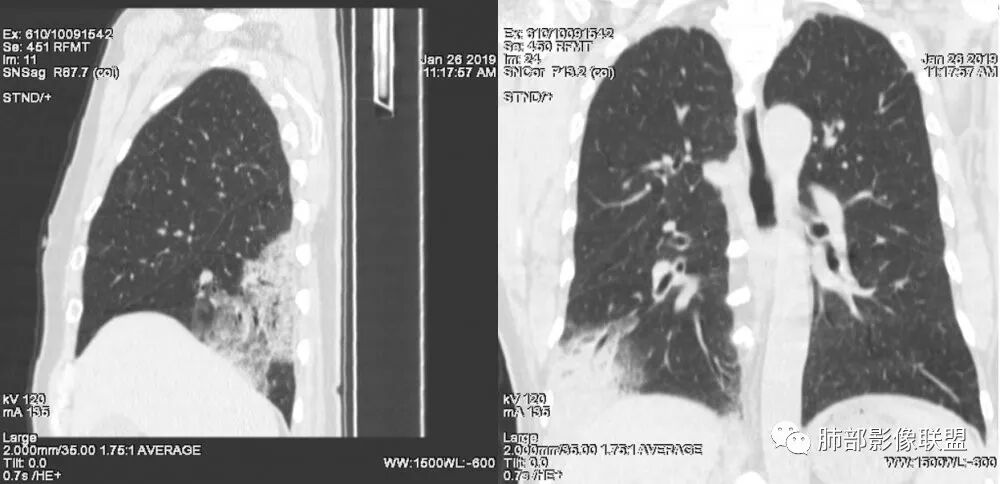

老年女性,右肺下叶沿胸膜下大片状高密度影,外周磨玻璃影,边界较清,内可见蜂窝征及支气管充气征,考虑肺炎型肺癌。

老年女性,咳嗽咳痰病史,右肺下叶大片磨玻璃实变影,胸膜下分布,支气管进入后扩张、僵直,磨玻璃影边界清楚,考虑粘液腺癌。鉴别肺炎。

右肺下叶基底段靠胸膜实变/磨玻璃混杂密度影,边界清楚,内见多发空泡(蜂窝样趋势改变?); 临床:咳嗽咳痰,无发热、胸痛; 考虑腺癌:无发热,感染性病变不首先考虑;部分层面形态类楔形,鉴别肺栓塞

老年女性,右下肺实变影,病灶里有小叶内间质增厚,周围GGo,支气管扩张,粘液性腺癌?淋巴瘤?

中年女性,咳嗽咳痰。右肺下叶片状高密度影,部分实性密度,周围见边界清晰磨玻璃影,内见小空泡,实性区部分支气管堵塞,有重力效应,考虑肺炎型肺癌,建议查痰脱落细胞。

老年人,右肺下叶斑片状阴影,病灶有膨胀性,边缘可见磨玻璃影,其边界清晰,内见僵硬的支气管,部分支气管扩张,首先考虑占位性病变,粘液性腺癌可能。鉴别感染性病变,后者边缘多有收缩性改变或者平直,内部支气管走形自然。

中年女性,右肺下叶沿胸膜下大片状高密度影,实变加GGO,外朝内发展,边界较清,内可见蜂窝征及枯树征,考虑肺炎型肺癌。

右肺病灶,病灶较大,实性+周边ggo,边界清晰,胸膜下分布,长轴平行于胸膜,内部支气管充气征,因不发热,暂不考虑感染性病变,支持肺炎型肺癌。

女性,咳嗽咳痰不发烧,右下外基底段实变影,边缘清楚GGO,有充气支气管征,枯树枝不明显,由外向内;诊断:肺炎型肺腺癌;鉴别:1、肺栓塞(外型神似,但无胸痛丶咯血);2丶肺炎

老年女性,右下肺实变影,糊墙,外朝内发展,病灶里有小叶内间质增厚,周围边界清楚了GGO,支气管扩张明显,考虑粘液癌;不符合点,支气管扩张太厉害了,鉴别淋巴瘤。

患者中年女性,咳嗽咳痰就诊。胸部CT:右肺下叶后基底段片状实变影,由胸膜向内发展呈扇形,病灶里有小叶内间质增厚、蜂窝状影,周围边界清楚GGO,内可见扩张支气管,淋巴结无明显肿大。综合符合粘液腺癌。

老年女性;右下肺混合实变影,呈楔形改变,边缘清晰,支气管进入且扩张,蜂窝状改变,考虑粘膜相关淋巴瘤,鉴别粘液腺癌,肺栓塞。

女,55咳嗽咳痰,右肺下叶片状实变,磨玻璃影及蜂窝影,考虑粘液腺癌。

老年女性,咳嗽、咳痰。右肺下叶沿胸膜下大片状高密度影,外周磨玻璃影,边界较清,小空泡,蜂窝征及支气管充气征,叶间裂串珠征,考虑:肺炎型肺癌,鉴别:肺克,链球菌,NTM等感染。

右肺下叶大片状影,密度不均匀,部分实变部分磨玻璃,大部分病灶尚清晰,其内支气管稍扩张,中年女性,首先考虑粘液腺癌,待鉴别淋巴瘤,常规抗炎治疗后复查。

中年女性,右肺下叶实变,近似扇形,外朝内发展趋势,外围紧贴胸膜面,中心密度略高,边缘密度略低,病灶内支气管略扩张。考虑肺炎型肺癌。常规建议抗炎治疗后复查,如无变化或变化不明显,建议穿刺活检。

胸膜下,实变,毛玻璃影,囊,边界清,枯枝,粘液腺。

老年女性,右肺下叶大片实变,小叶间隔及小叶内间隔增厚,边界较清,其内支气管似乎可见稍扭曲,分支减少。考虑1.肺炎型肺癌2.结合临床除外类脂性肺炎。

起源于胸膜下,实性成分,边缘Ggo,边界清晰,内可见小叶间隔增厚,粘液腺癌可能。建议先消炎后复查。

右肺下叶胸膜下大片状MGGO,其内结构紊乱,可见空泡征,病灶内近端支气管扩张,远端闭塞,形态不规则,边界部分清楚,部分似清非清,考虑粘液腺癌,鉴别淋巴瘤

该病灶主病灶位于胸膜下(肋膈角处),边缘膨隆改变,周围毛玻璃,边界清楚,病灶内支气管僵直,轻度扩张,小分支无,符合枯树枝改变,有多发小空泡(难与支气管区别),应该符合肺炎性肺癌,但无蜂窝,没有增强无法判断有无粘液、血管特点,如果周围显示的空泡是支气管,其已达到远端,这些有符合炎性特点,工作中,我会先抗炎膨后复查再定。

这是潘老师说的外向内吗?右下实变,蜂窝,GGO,支气管变形迂曲,局部膨胀感,肺炎性肺癌,粘液腺癌可能。常规先抗炎再复查。鉴别淋巴瘤,淋巴瘤支气管一般不变形,壁光整,病程长。

1.本例病灶较大片混杂密度影,胸膜下分布为主(未沿着支气管分布),该分布特点可见于大叶性肺炎、干酪性肺炎、淋巴瘤及粘液腺癌等。可惜未提供增强扫描图像。

2.病灶示中央实变区,周围GGO,可见明显小叶间隔增厚,GGO边界清楚,应当考虑到恶性病变的可能性。肺炎因炎性水肿及渗出,影像上边界常模糊不清,注意早期粘液腺癌可出现似清非清的边界。粘液腺癌因粘液成份较多,密度一般偏低,纵隔窗病灶常会消隐或范围会明显缩小,这不同于炎性实变。

3.病灶内支气管走形略显僵直,侧支少(粘液阻塞),也符合肺腺癌的枯树枝征。而大叶性肺炎的支气管是管壁光整、通畅、自然,结核的支气管常常壁增厚,甚至狭窄后扩张;

4.患者临床症状不重,临床炎性指标不高,结合肺内影像,应警惕肺炎型肺癌。